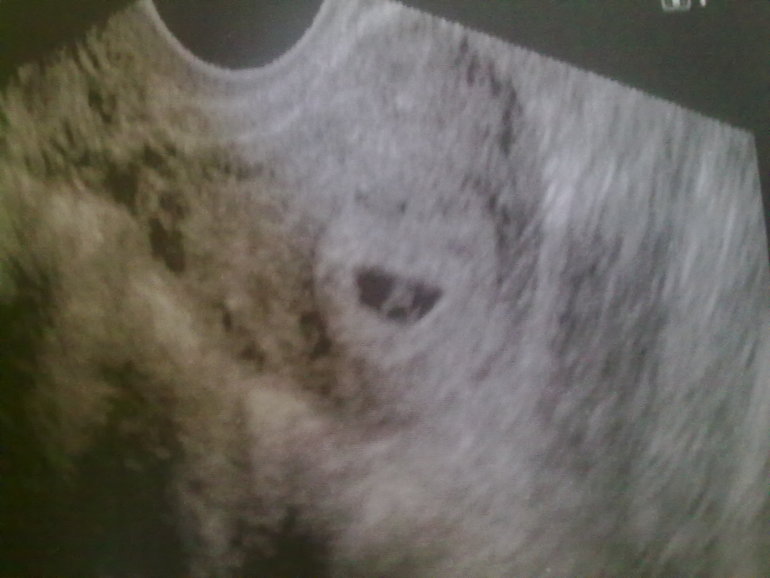

Итак лежу, врач смотрит молча, долго смотрит, молчит, я уже переживать начинаю, а она говорит такая "Ого, как сердце уже колотится!")))) Моему счастью не было предела! Показывает мне, но как жаль что с положения лежа плохо видно, но все же я рассмотрела сердцебиение!!!

Вот мы:

Правда, как я не просила, размеры не померили, не знаю почему они не хотят тут мерить. И меня еще не выписывают, так как есть угроза из-за тонуса. Говорит, что плодное яйцо должно быть круглым, а у меня приплюснутое. Но на выходные домой отпустят)